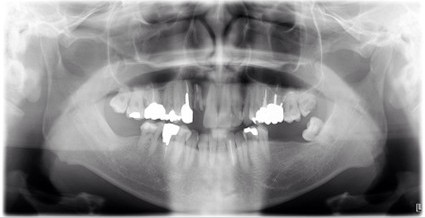

| 主訴 | 膿で腫れて痛みが強い、他の歯医者で抜歯しかないと言われ相談で来院 |

| 状態 | 自発痛もかなり強く、写真のように膿が溜まって腫れ上がっている状態 |

| 治療内容 | X写真から根先部の根先病変が原因と思われるため、根管治療を行った。 骨成長因子を用いて、骨の再生を促した。 結果、2年経過後病変の大きさが1/3まで縮小し、骨の再生が認められる。 本人も症状や違和感がなくなったため、一時的に補綴物をセラミックで行った。 |

| 料金 | 根管治療10万円、ファイバーコア2万円、EーMAX11.5万円 |